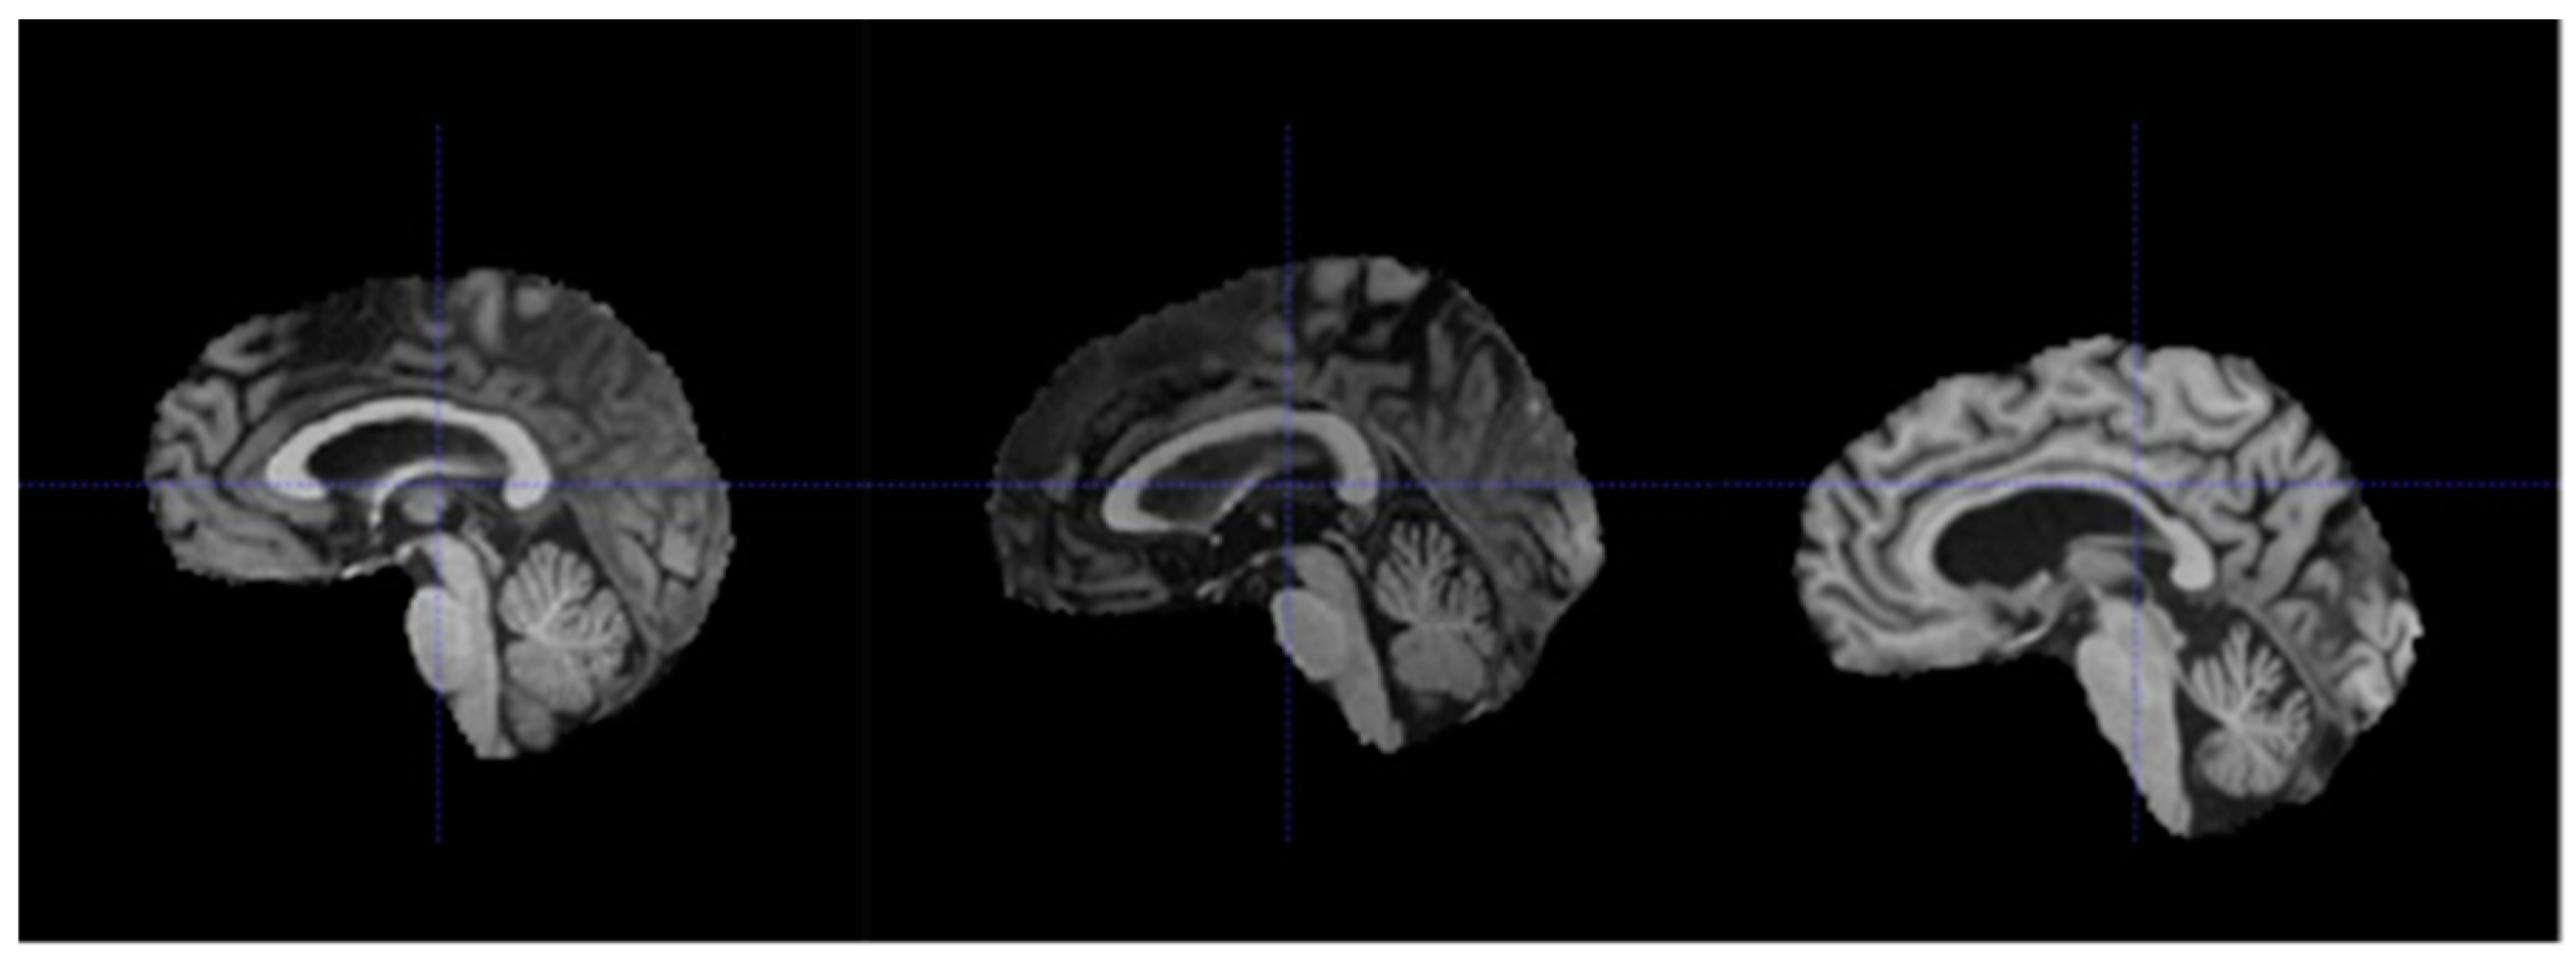

Generally speaking, each affine transformation matrix (and its inverse) represents the series of transformations required to map each voxel in the volume to a standardized reference space within the scanner [40]. In the HarP dataset, there were 15 subjects with different affine transformation matrices from the rest. One possible explanation is that for these 15 subjects, their MRI scans were taken using a tilted scan angle to obtain oblique scans [37]. Oblique scans are usually used to reduce noise caused by artifacts in the path of the magnetic field, such as air and water within the head of each subject. The use of oblique scans in these 15 subjects meant that even though registration was performed for these subjects, their MRI volumes may still not be as well aligned as those of the other 115 subjects [37]. This was further supported by our observations shown in Figure 5, in which the brain was situated lower in a MRI volume associated with a different affine transformation matrix.

Figure 5.

Sagittal views from subjects 067_S_1253 (left), 094_S_1293 (middle), and 023_S_0604 (right). Subject 023_S_0604 had a different affine matrix from the other two subjects.